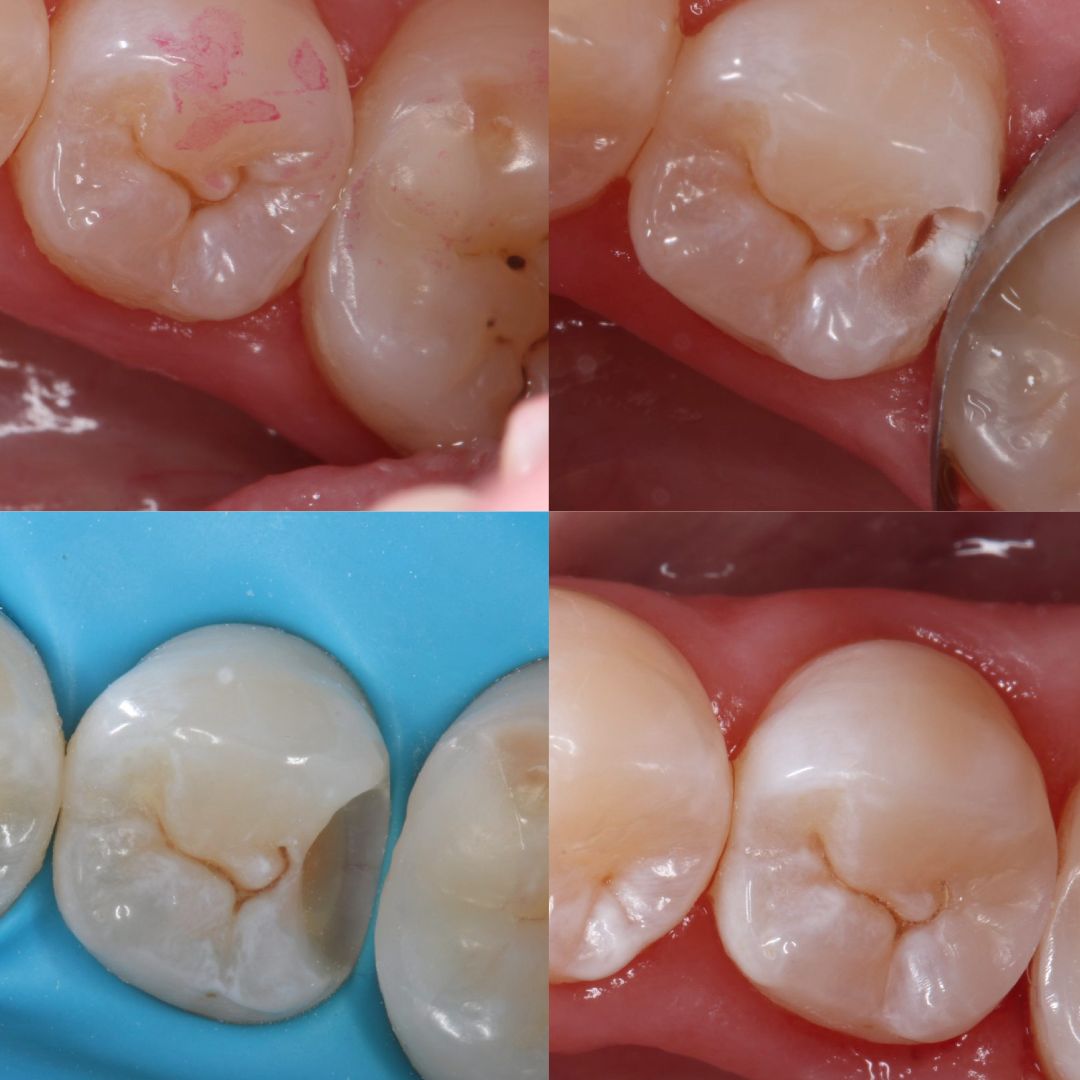

Jej pasją jest leczenie zachowawcze, wypełnienia z jej ręki są małymi dziełami sztuki, idealnie i anatomicznie wykończonymi. Precyzja i cierpliwość w sposobie pracy w połączeniu z wysokim poczuciem estetyki umożliwiły tej naturalny rozwój w kierunku stomatologii estetycznej. Dr Valeriia wykonuje precyzyjne kompozytowe odbudowy zębów przednich, bondingi oraz prace „z ręki”.

Doktor uważa, że obraz mówi więcej niż słowa, zapraszamy do zapoznania się z galerią jej prac.